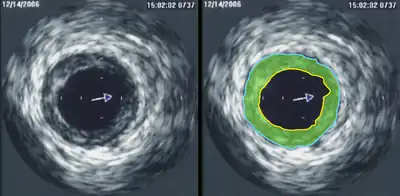

Intravascular ultrasound (IVUS) uses a specially designed catheter with a miniaturized ultrasound probe attached to its distal end, which is then threaded inside a blood vessel. The proximal end of the catheter is attached to computerized ultrasound equipment and allows the application of ultrasound technology, such as a piezoelectric transducer or capacitive micromachined ultrasonic transducer, to visualize the endothelium of blood vessels in living individuals.[11]